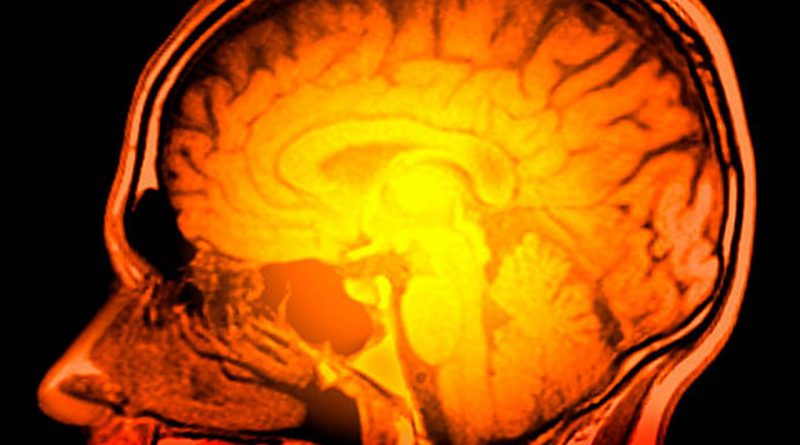

Questa condizione viene spesso definita acqua sul cervello. Ogni singola persona ha un fluido che attutisce il suo cervello, un po ‘come un ammortizzatore. Ma ci sono alcuni casi in cui il liquido cerebrospinale può aumentare e questo sta causando una maggiore pressione sul cervello. Succede quando il sistema naturale di drenaggio e assorbimento di CFS extra non funziona correttamente. I ventricoli si allargano per accogliere il liquido extra e quindi premono su diverse parti del cervello che causano molti sintomi diversi.

I trainer di yoga raccomandano di non interrompere la respirazione. Lo yoga può aiutare tutte le persone a sentirsi meglio e più in salute. Sappiamo che l’idrocefalo è acqua nel cervello. Questa è una condizione medica in cui vi è un accumulo anormale di CFS nei ventricoli del cervello. Questo può accadere quando c’è un ostacolo al flusso di CFS per molte ragioni diverse. Ci sono alcuni studi in cui si dice che la regolazione di questo flusso può portare a nuove procedure diagnostiche e terapeutiche.